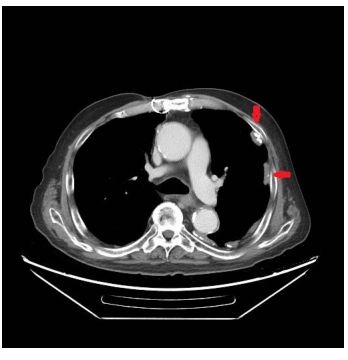

30. 72歲海軍退休輪機士官長,長年在軍艦輪機房工作。最近因為喘,在門診就診,胸部X光異常,於是接受胸部電腦斷層檢查如附圖,下列何者敘述為是?

(1) 電腦斷層顯示為胸膜斑(pleural plaques)

(2) 與工作環境息息相關

(3) 不會引起肺癌

(4) 與胸腔間皮瘤高度相關

(5) 抽煙對於癌症的發生率不會有加成效果

(A) (1)+(2)+(3)(B) (2)+(3)+(4)(C) (3)+(4)+(5)(D) (1)+(2)+(4)(E) (1)+(2)+(5)